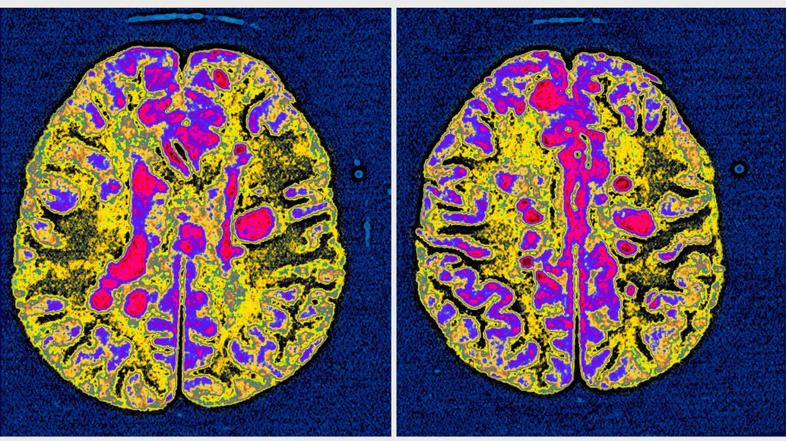

Avtoimuna bolezen, ki povzroča vnetje v osrednjem živčevju.

Za multiplo sklerozo (MS) v glavnem zbolevajo ljudje v najaktivnejše obdobju življenja, od dvajsetega do štiridesetega leta starosti. Gre za najpogostejše nevrološko obolenje za katerega ne poznamo ne vzroka in ne zdravila. Je bolezen centralnega živčnega sistema in je najštevilčnejša bolezen nevro imunskega sistema pri nas.

MS v devetdesetih odstotkih povzroča težko in najtežjo invalidnost, je neozdravljiva, zato bolnikom ostane le blažitev težav, ki so posledica že nastalih okvar in poškodb.

Svetovni dan multiple skleroze, 30. maj, letos poteka pod geslom Povežimo se. Mednarodna zveza za multiplo sklerozo s sedežem v Londonu želi s svetovnim dnevom, povečati ozaveščanje o tej avtoimuni bolezni, ki povzroča vnetje v osrednjem živčevju.